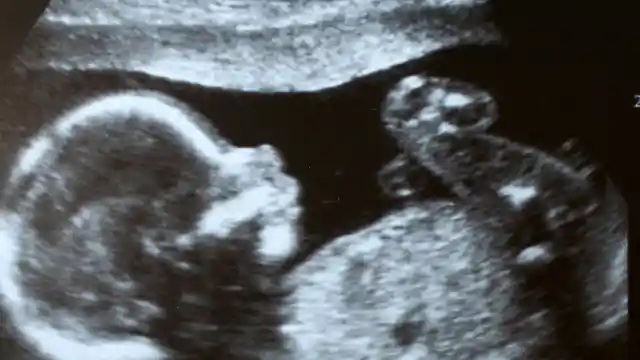

Grávida

“O que é?”, Holly finalmente perguntou, com a voz misturando medo e frustração. “O que há de errado?” A Dra. Linares virou a tela para Holly. “Você não vai acreditar nisso”, ela começou, com a voz firme, mas tingida de emoção. “Mas você está grávida.”

A gravidez era a última coisa que Holly esperava. Na idade deles, a ideia de ter um filho era um sonho distante, que eles haviam lamentado e, por fim, aceitado como impossível. A notícia era chocante, um raio caído do céu que destruiu sua vida previsível.

O ultrassom inicial com a Dra. Linares a deixou atordoada, com descrença misturada a uma crescente sensação de admiração. A vida nesta fase poderia trazer uma surpresa tão monumental? Em busca de clareza e compreensão, Holly procurou o Dr. Ethan Carter, um renomado especialista que ela havia consultado 11 anos antes.